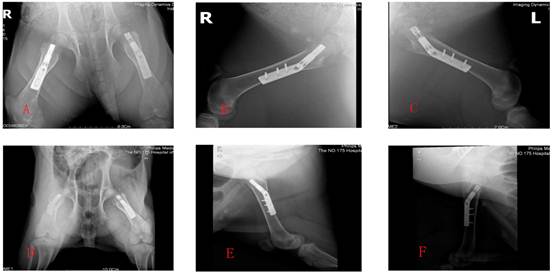

Figure 3

A,B,C showed the X-ray photographs at week 8 postoperatively; D,E,F showed the X-ray photographs at week 16 postoperatively.

No pigs had postoperative complications and all were able to walk on the 3rd postoperative day and had stable fixation of their femurs at 8 and 16 weeks. At 8 and 16 weeks postoperatively, we assessed the experimental animals by X-rays, CT scans and postmortem visual appraisal of evidence of bone healing (Figures 3, 4, 5).

Eight weeks postoperatively, bone healing according to the Lane-Sandhu score was better in the Hb-DHS than in the DHS group, this difference being statistically significant (Z test −2.530, P < 0.05) (Tables 2 and 3). The Vp and BMD were also significantly better in the Hb-DHS than in the DHS group (Z test −2.337 for Vp, −2.291 for BMD on the tension side and −2.309 for BMD on the pressure side, P < 0.05). Sixteen weeks postoperatively, bone healing according to the Lane-Sandhu score was still significantly better in the Hb-DHS than the DHS group (Z test −2.247, P < 0.05). The Vp and BMD were also significantly better in the Hb-DHS than the DHS group (Z test −2.336 for Vp, −2.247 for BMD on the tension side, −2.309 for BMD on the pressure side, P < 0.05) (Tables 2 and 3).